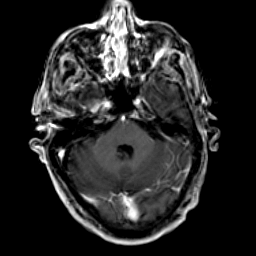

Glioma Overlay -- Slice #5

[Home][Help][Clinical] Slice 5